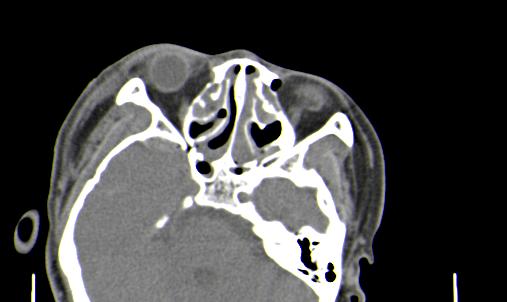

以下是引用皎皎白驹在2006-11-29 8:48:00的发言:[br]影像表现:双侧筛窦和上颌窦、鼻腔内均密度增高,右侧视神经增粗、弯曲,左筛窦顶部筛板及右侧纸板近视神经孔区可见骨折线。[br]结合临床表现考虑:右侧筛窦纸板近视神经孔区骨折致右侧视神经损伤。最好做个眼眶冠状扫描,更明确右侧视神经管是否狭窄。

以下是引用w_jianhua在2006-11-29 10:07:00的发言:[br]影像表现:双侧筛窦和上颌窦、鼻腔内均密度增高,右侧视神经增粗、弯曲,左筛窦顶部筛板及右侧纸板近视神经孔区可见骨折线。[br]结合临床表现考虑:右侧筛窦纸板近视神经孔区骨折致右侧视神经损伤。最好做个眼眶冠状扫描,更明确右侧视神经管是否狭窄。 [br] [br]支持[br]

以下是引用守望可可西里在2006-11-29 9:46:00的发言:[br][quote]以下是引用皎皎白驹在2006-11-29 8:48:00的发言:[br]影像表现:双侧筛窦和上颌窦、鼻腔内均密度增高,右侧视神经增粗、弯曲,左筛窦顶部筛板及右侧纸板近视神经孔区可见骨折线。[br]结合临床表现考虑:右侧筛窦纸板近视神经孔区骨折致右侧视神经损伤。最好做个眼眶冠状扫描,更明确右侧视神经管是否狭窄。